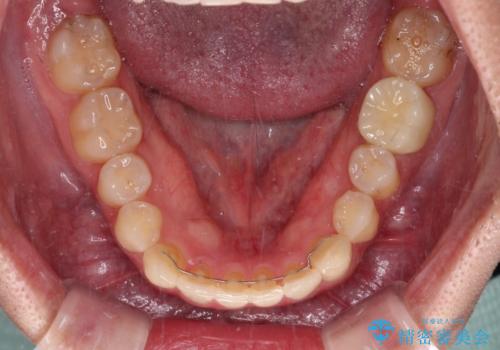

- 前歯のクロスバイトを気にして来院された患者様です。

骨格的には問題がなかったため、インビザラインを用いて咬み合わせを改善していくこととしました。

インビザライン特有の、奥歯の咬み合わせの問題もなく、しっかりと歯列を改善することができました。

舌側転位している上顎側切歯(内側に引っ込んでいる真ん中から2番目の歯)は、インビザラインが最も移動を苦手とする歯であり、これ以上の改善を望まれる場合にはワイヤー矯正、あるいはワイヤー矯正の併用をお勧めいたします。